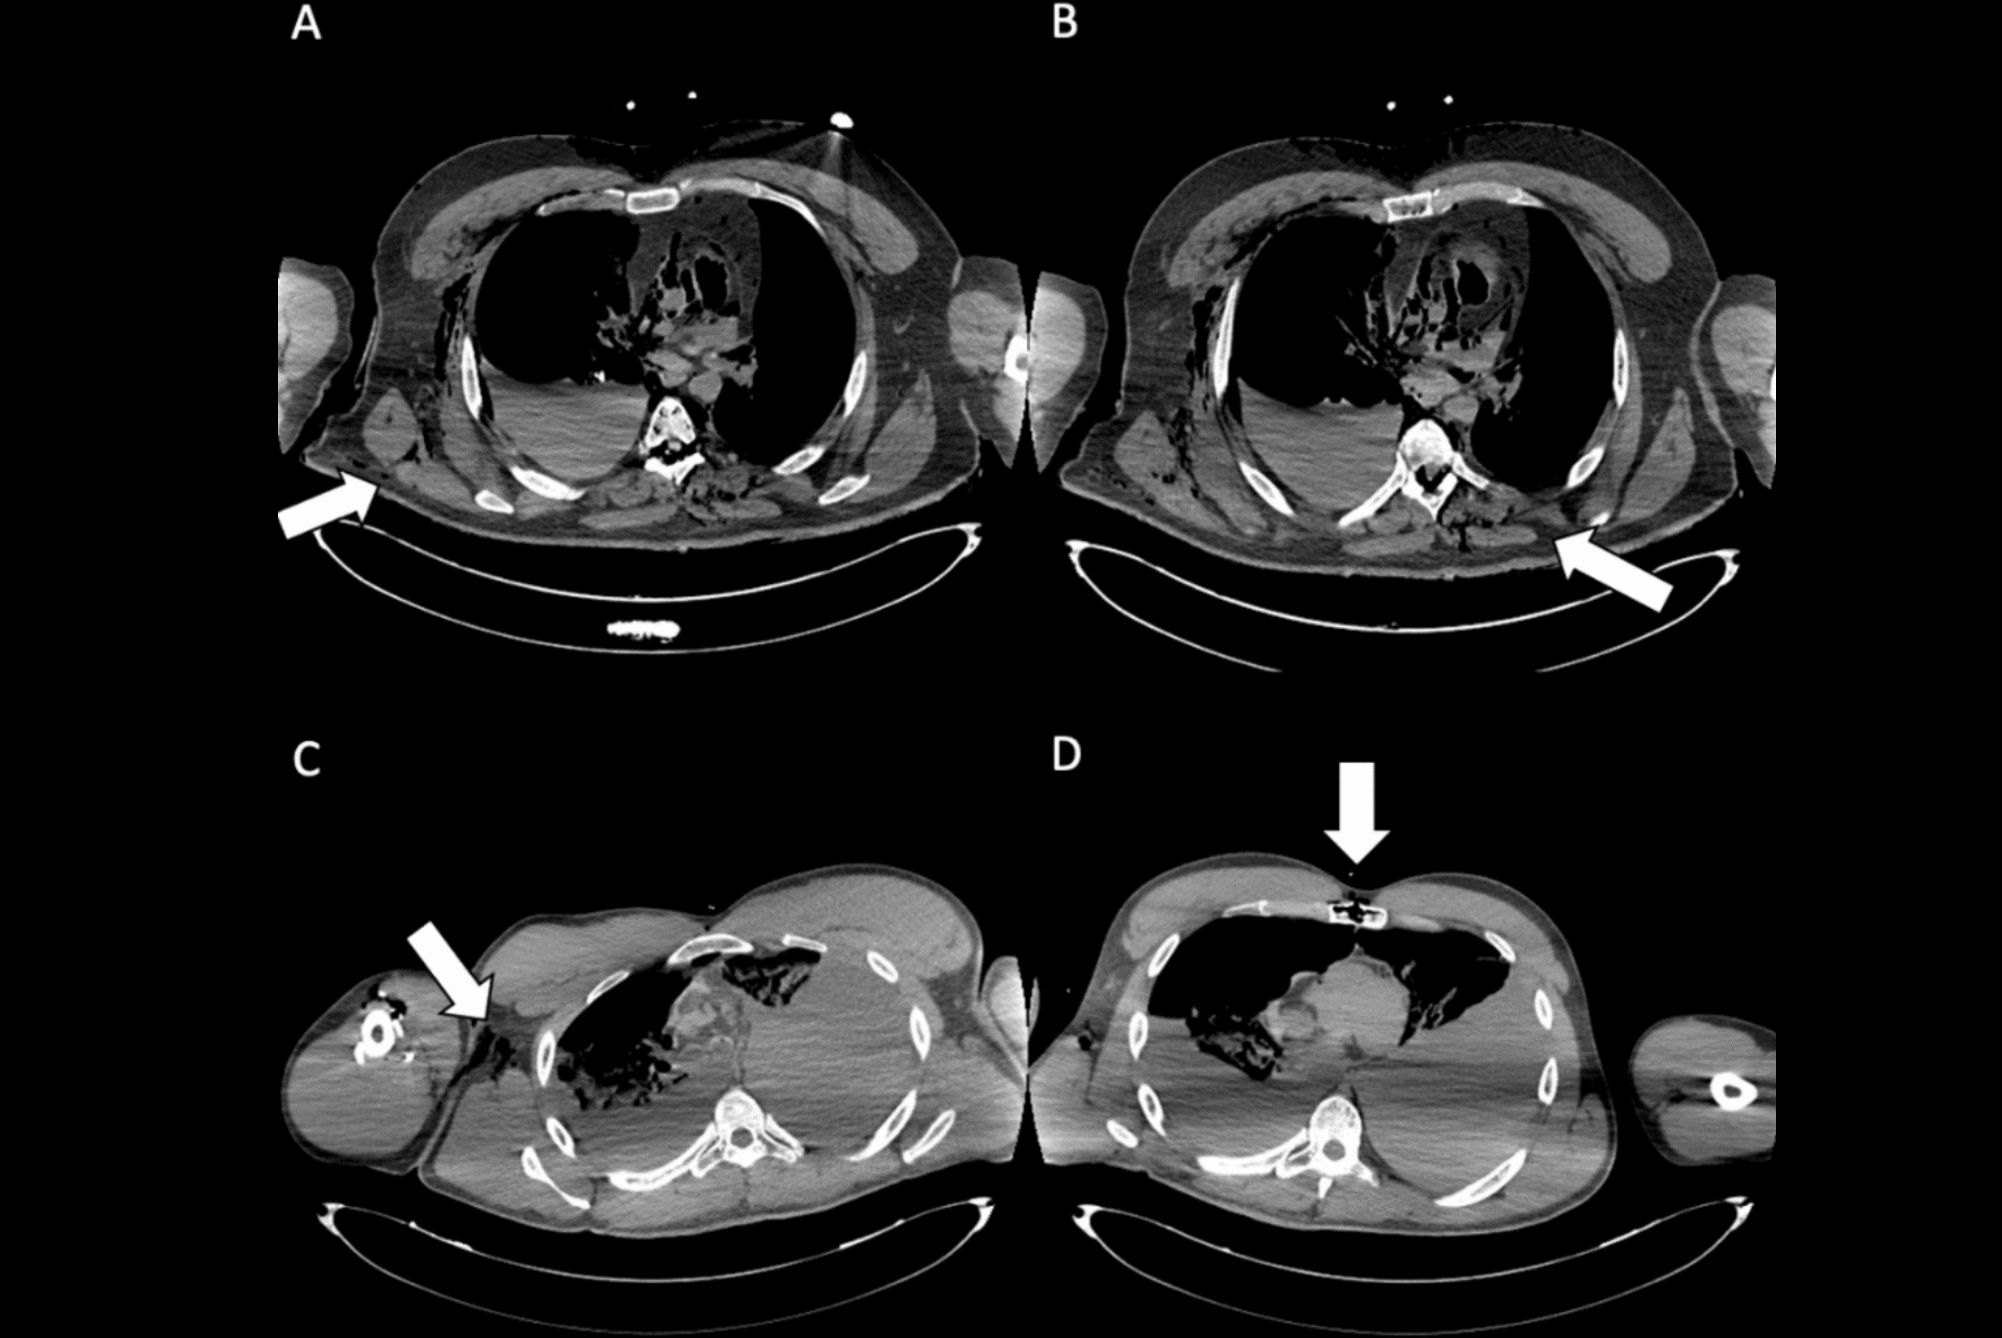

Postmortem multislice CT explorations of two different unknown bodies, with reconstructions in volume-rendering technique mode permitting detection of metal. Above: Chest level: Detection of metallic foreign bodies secondary to surgery of the neck (metallic surgical clips due to surgery of the thyroid) and the chest (metallic wire on the sternum secondary to heart surgery). Below: Left foot: Detection of two surgical screws within the first metatarsal secondary to surgery. Images courtesy of Dr. Fabrice Dedouit, PhD.

"MSCT is effective in identifying infectious lesions, and is more informative than plain x-rays. Infectious processes can affect bones, teeth, and also soft tissues, so MSCT can be very helpful in study of mummies," the researchers noted. "More rarely, bone tumors may be observed, or features secondary to metabolic changes or anemia such as cribra orbitalia, Harris lines, osteopenia, or osteoporosis. Foreign bodies may also be detected within bones."